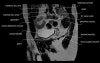

- Axial section

Axial T1 large field of view allows for evaluation of both hips simultaneously, particularly the acetabulae.

Axial PD fat suppressed is sensitive to fluid that may be present with avascular necrosis or stress fractures, while maintaining high a SNR.